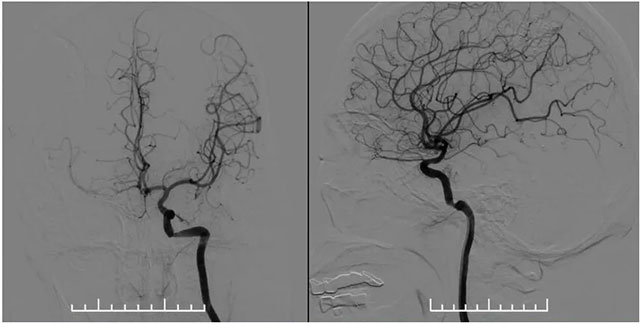

▲ 左侧颈内动脉造影见岩骨段远端狭窄,右侧大脑中动脉由左侧颈内部分代偿

MR示双侧基底节区及右侧顶叶凸面小梗塞(部分软化灶形成)轻度脑白质疏松,MR-tof 可见左侧颈内动脉岩骨段狭窄。DSA血管造影:左侧椎动脉支架内再狭窄,左侧颈内动脉造影见岩骨段远端狭窄,右侧大脑中动脉由左侧颈内部分代偿,右侧颈动脉造影提示右侧颈内动脉闭塞。